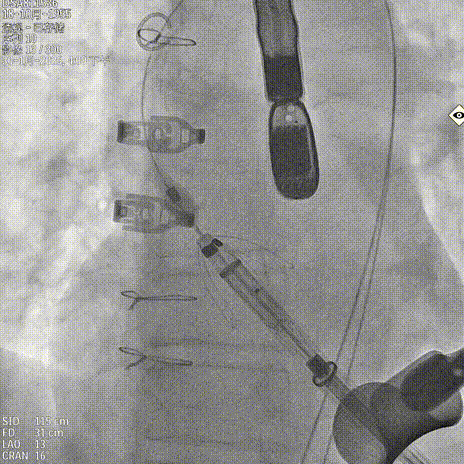

释放瓣膜

锁丝脱钩

撤出输送器

术后造影 反流消失